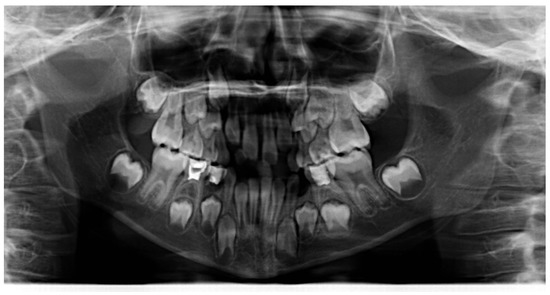

3.1. Clinical Case #1